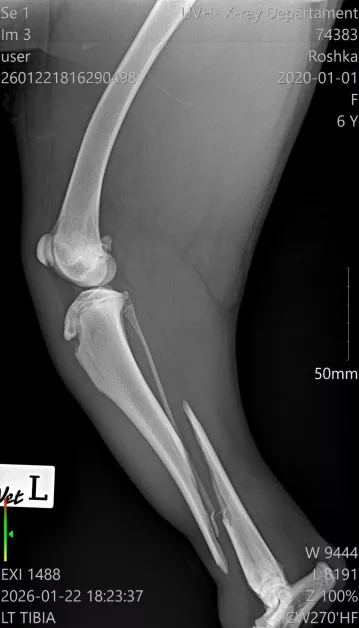

Диагнозата е тежка – две сериозни фрактури на задните крайници в областта на пищялите, с разместване и травмирани меки тъкани. По думите на ортопеда съществува реален шанс фрактурите да бъдат фиксирани с импланти и винтове, което би позволило на Рошка отново да проходи.